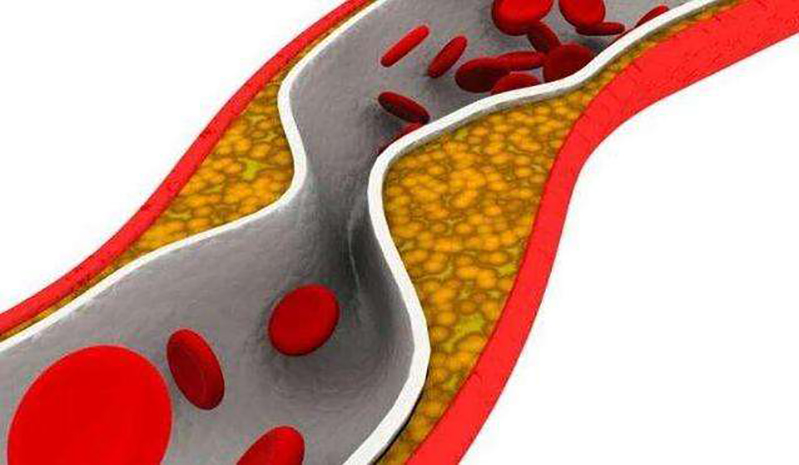

对于血脂检查的各项指标来说,甘油三酯是很重要的一个检查项,发现甘油三酯高了怎么办?可以通过运动锻炼降下来吗?如何运动才能事半功倍?相比于血脂检查的其他胆固醇指标......